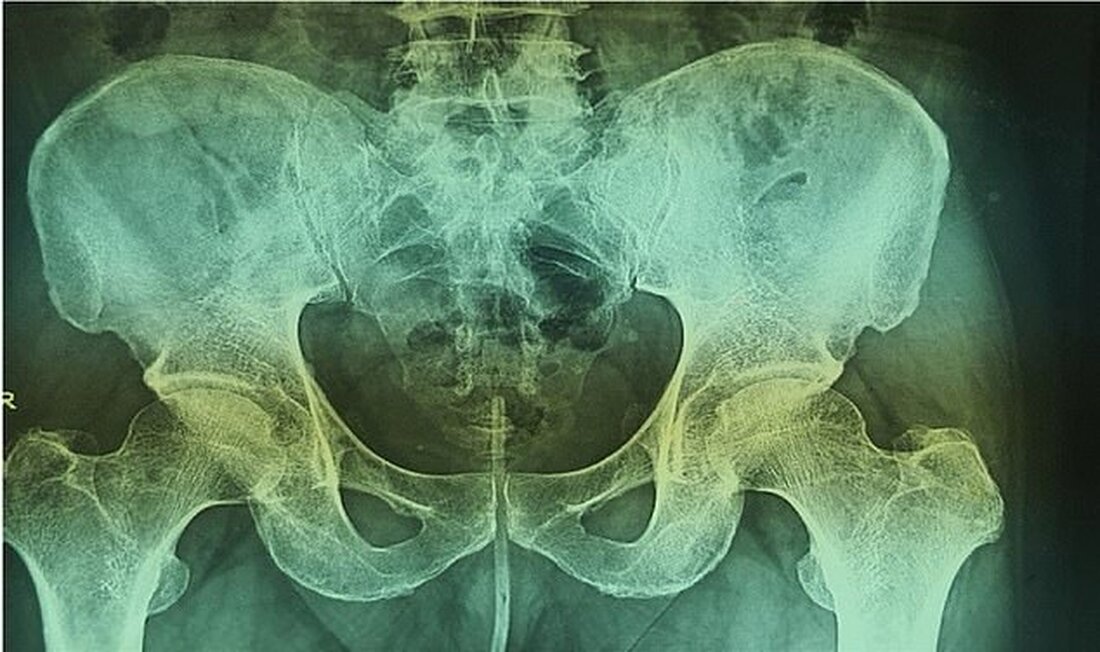

Eine Röntgenaufnahme ergab, dass sich der Draht bis zur Harnröhre des Mannes bis zu seiner Blase erstreckt hatte.

Dieses Röntgenbild zeigt den Draht (Mitte) in der Harnröhre des Mannes und erstreckt sich bis zu seiner Blase